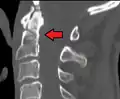

Type 3 odontoid fracture

Type 2 dens fracture